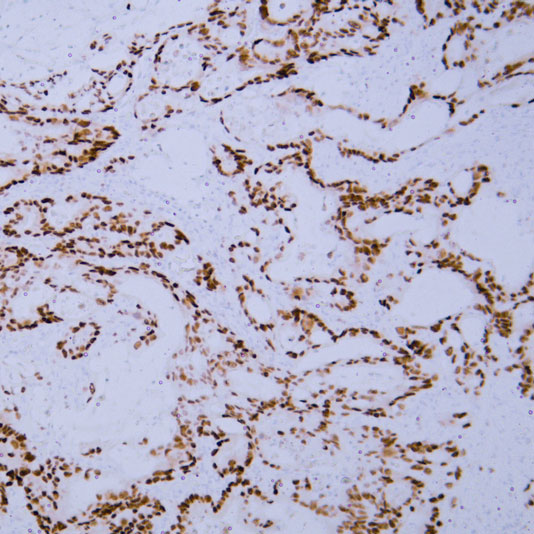

Explore Our Recommended Popular Products

30,000+ high- quality products available online

Primary Antibodies, Secondary Antibodies, mIHC Kits, ELISA Kits, Proteins, Molecular Biology Products,Cell Lines,Reagents ...